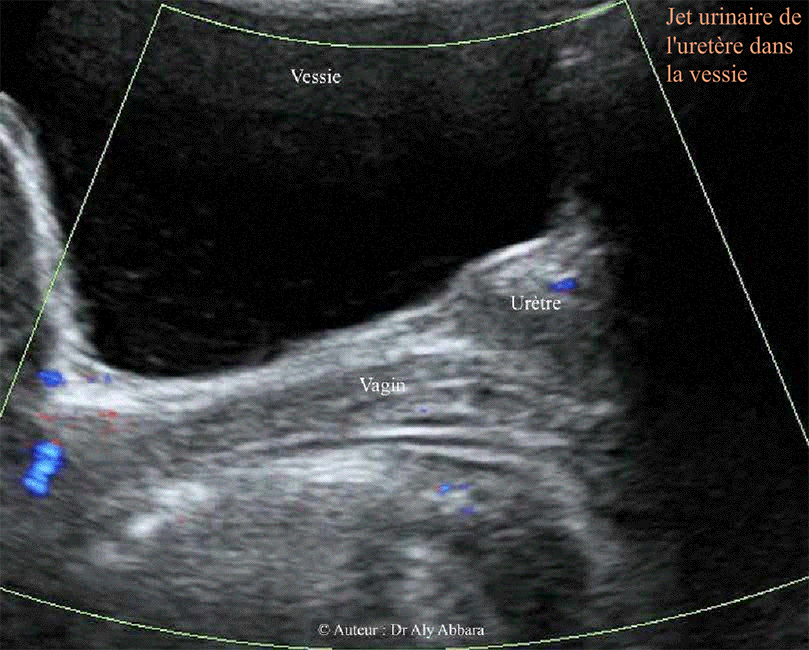

Vidéo échographique mettant en évidence l'aspect du Doppler couleur (Dynamic-Flow) du jet urinaire urétéral (en coupe sagittal) dans la cavité vésicale chez une femme de 27 ans.

Ces images évoquent bien le jet du cracheur du feu !!

Voir l'aspect du jet urinaire dans la vessie en coupe transverse de la vessie